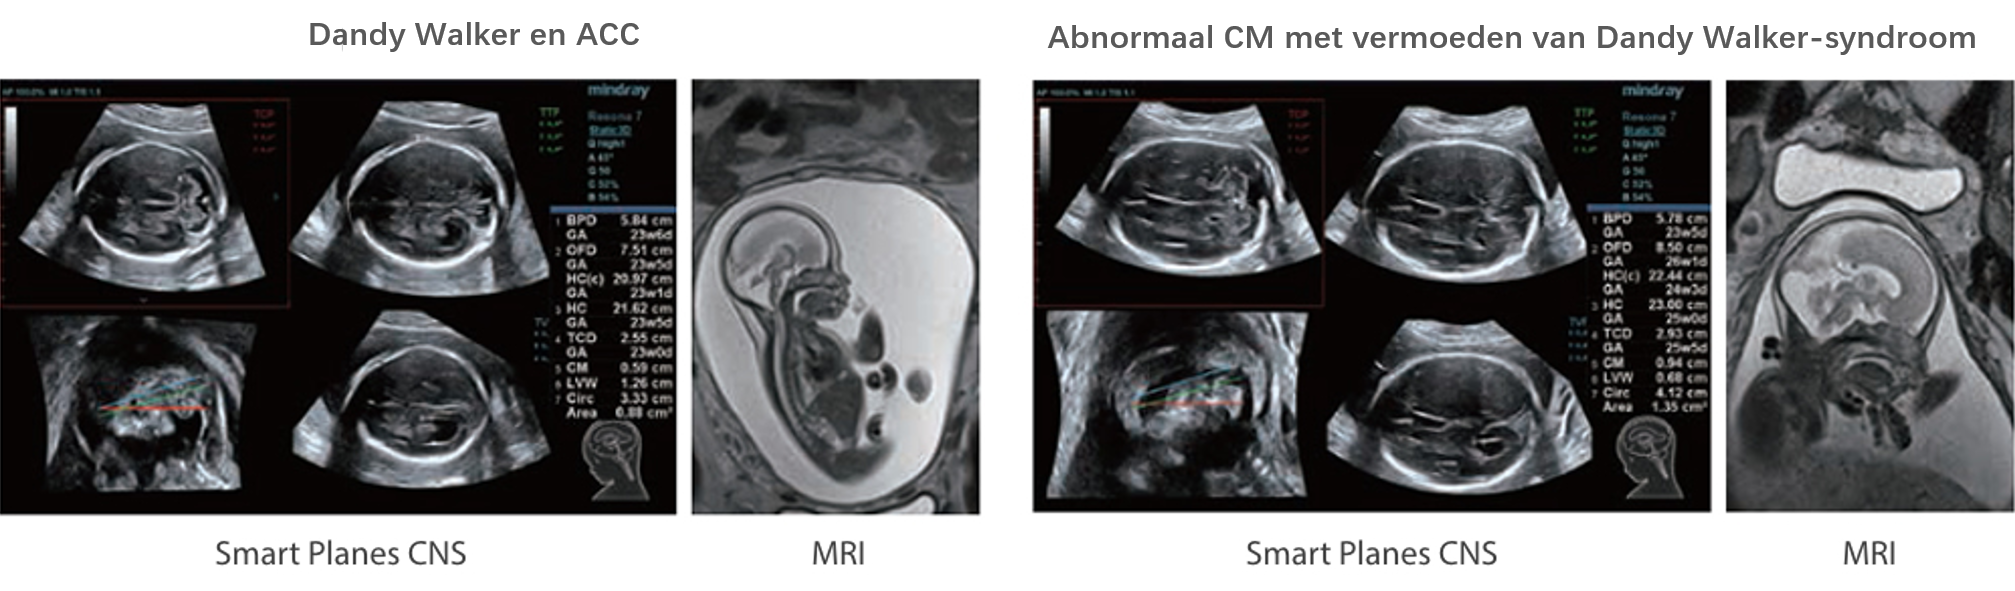

Naast de hoogwaardige beeldvormingskwaliteit verbetert de Resona 7 tevens de klinische onderzoeksmogelijkheden met de revolutionaire V Flow voor vasculaire hemodynamische evaluatie, en de intelligentste vlakacquisitie van een 3D-gegevenssets voor de diagnose van het foetale, centrale zenuwstelsel. Met zijn combinatie van de meest intu?tieve, op vingerbewegingen gebaseerde multi-aanrakingsbediening en alle essenti?le klinische functies loopt de Resona 7 voorop in de nieuwe golven van ultrasoundinnovatie.